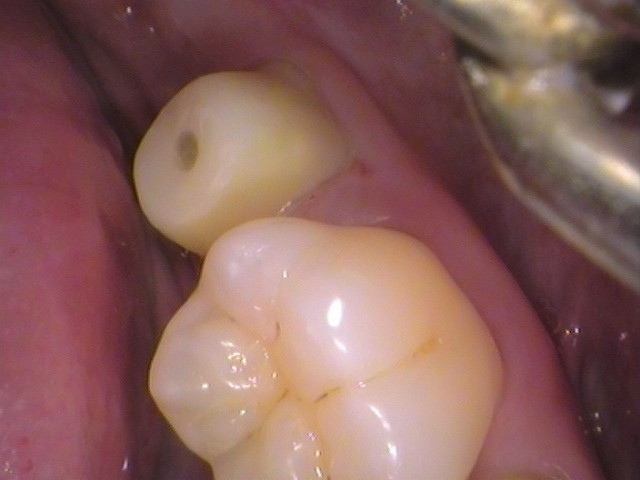

親知らずを抜歯した後の状態です。

大きな親知らずだったため、

大きな穴が空いています。

こちらは徐々に塞がってきますので問題はありません。